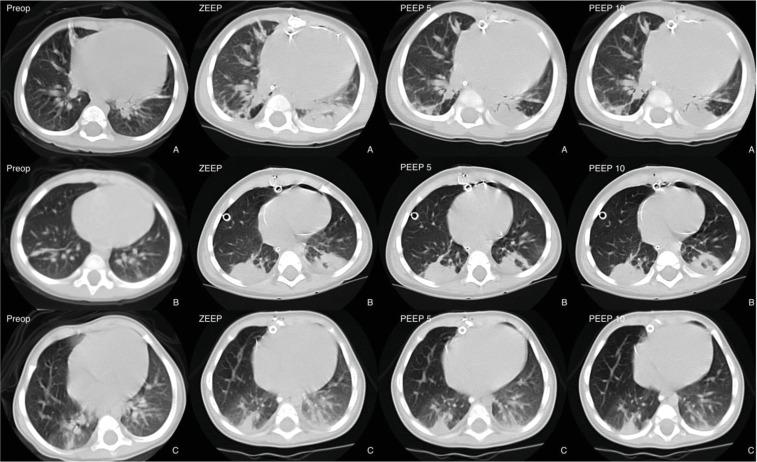

METHODS

Changes in lung aeration were investigated using volumetric computed tomography in 12 children with congenital acianogenic heart diseases and increased pulmonary flow who underwent total surgical repair under cardiopulmonary bypass. Computed tomography of the lungs was obtained preoperatively during spontaneous breathing and postoperatively during mechanical ventilation with positive end-expiratory pressure of 0, 5 and 10 cm HO. Gas and tissue lung volume and mass, as well non-aerated, poorly aerated and normally aerated lung compartments were measured.

Median age of patients was 18.3 months, (4 to 24 months), weight was 9.3 ± 2.3 kg. Cardiopulmonary bypass duration was 77 ± 26 minutes. Preoperatively, pulmonary volume was 545 mL (237‒753 mL), whereby tissue and gas volumes were 48.4% (41.7%‒59.6%), and 51.6% (40.4%‒58.3%), respectively. Non-aerated and normally aerated compartments accounted for 15% and 47.9% of lung tissue, respectively. Postoperatively, at zero PEEP, the non-aerated compartment increased to 27%, while normally-aerated compared decreased to 38.5%. Stepwise PEEP application restored normally aerated lung volume to preoperative levels but did not significantly reduce non-aerated parenchyma.

CONCLUSION

Loss of lung aeration was pronounced after surgical correction of congenital heart defects. PEEP up to 10 cm HO restored gas volume but failed to recruit the collapsed parenchyma. Ethical Approval CAPPesq n° 854/01.